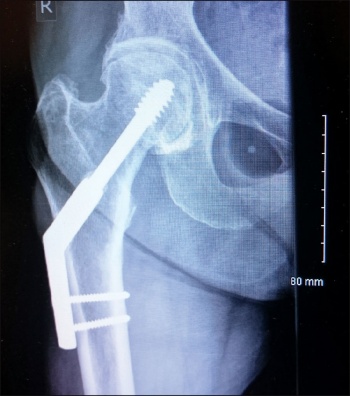

She was undergoing this treatment when in April 2015 she again had a low energy fall and was brought to hospital with pain right thigh and non-weight bearing. On x-ray she had DHS implant failure. She had the non-union of the original sub trochanteric fracture.

She was taken to theatre again and the DHS implant was removed. A long cephalomedullary nail was inserted. After that she was again started on physiotherapy.